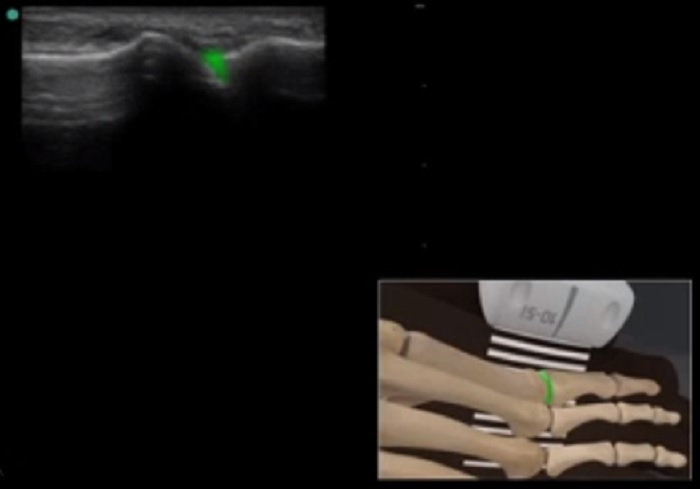

Foot & Ankle Metatarsalphalangeal Joint Image

Highlighted Area: Metatarsalphalangeal Joint